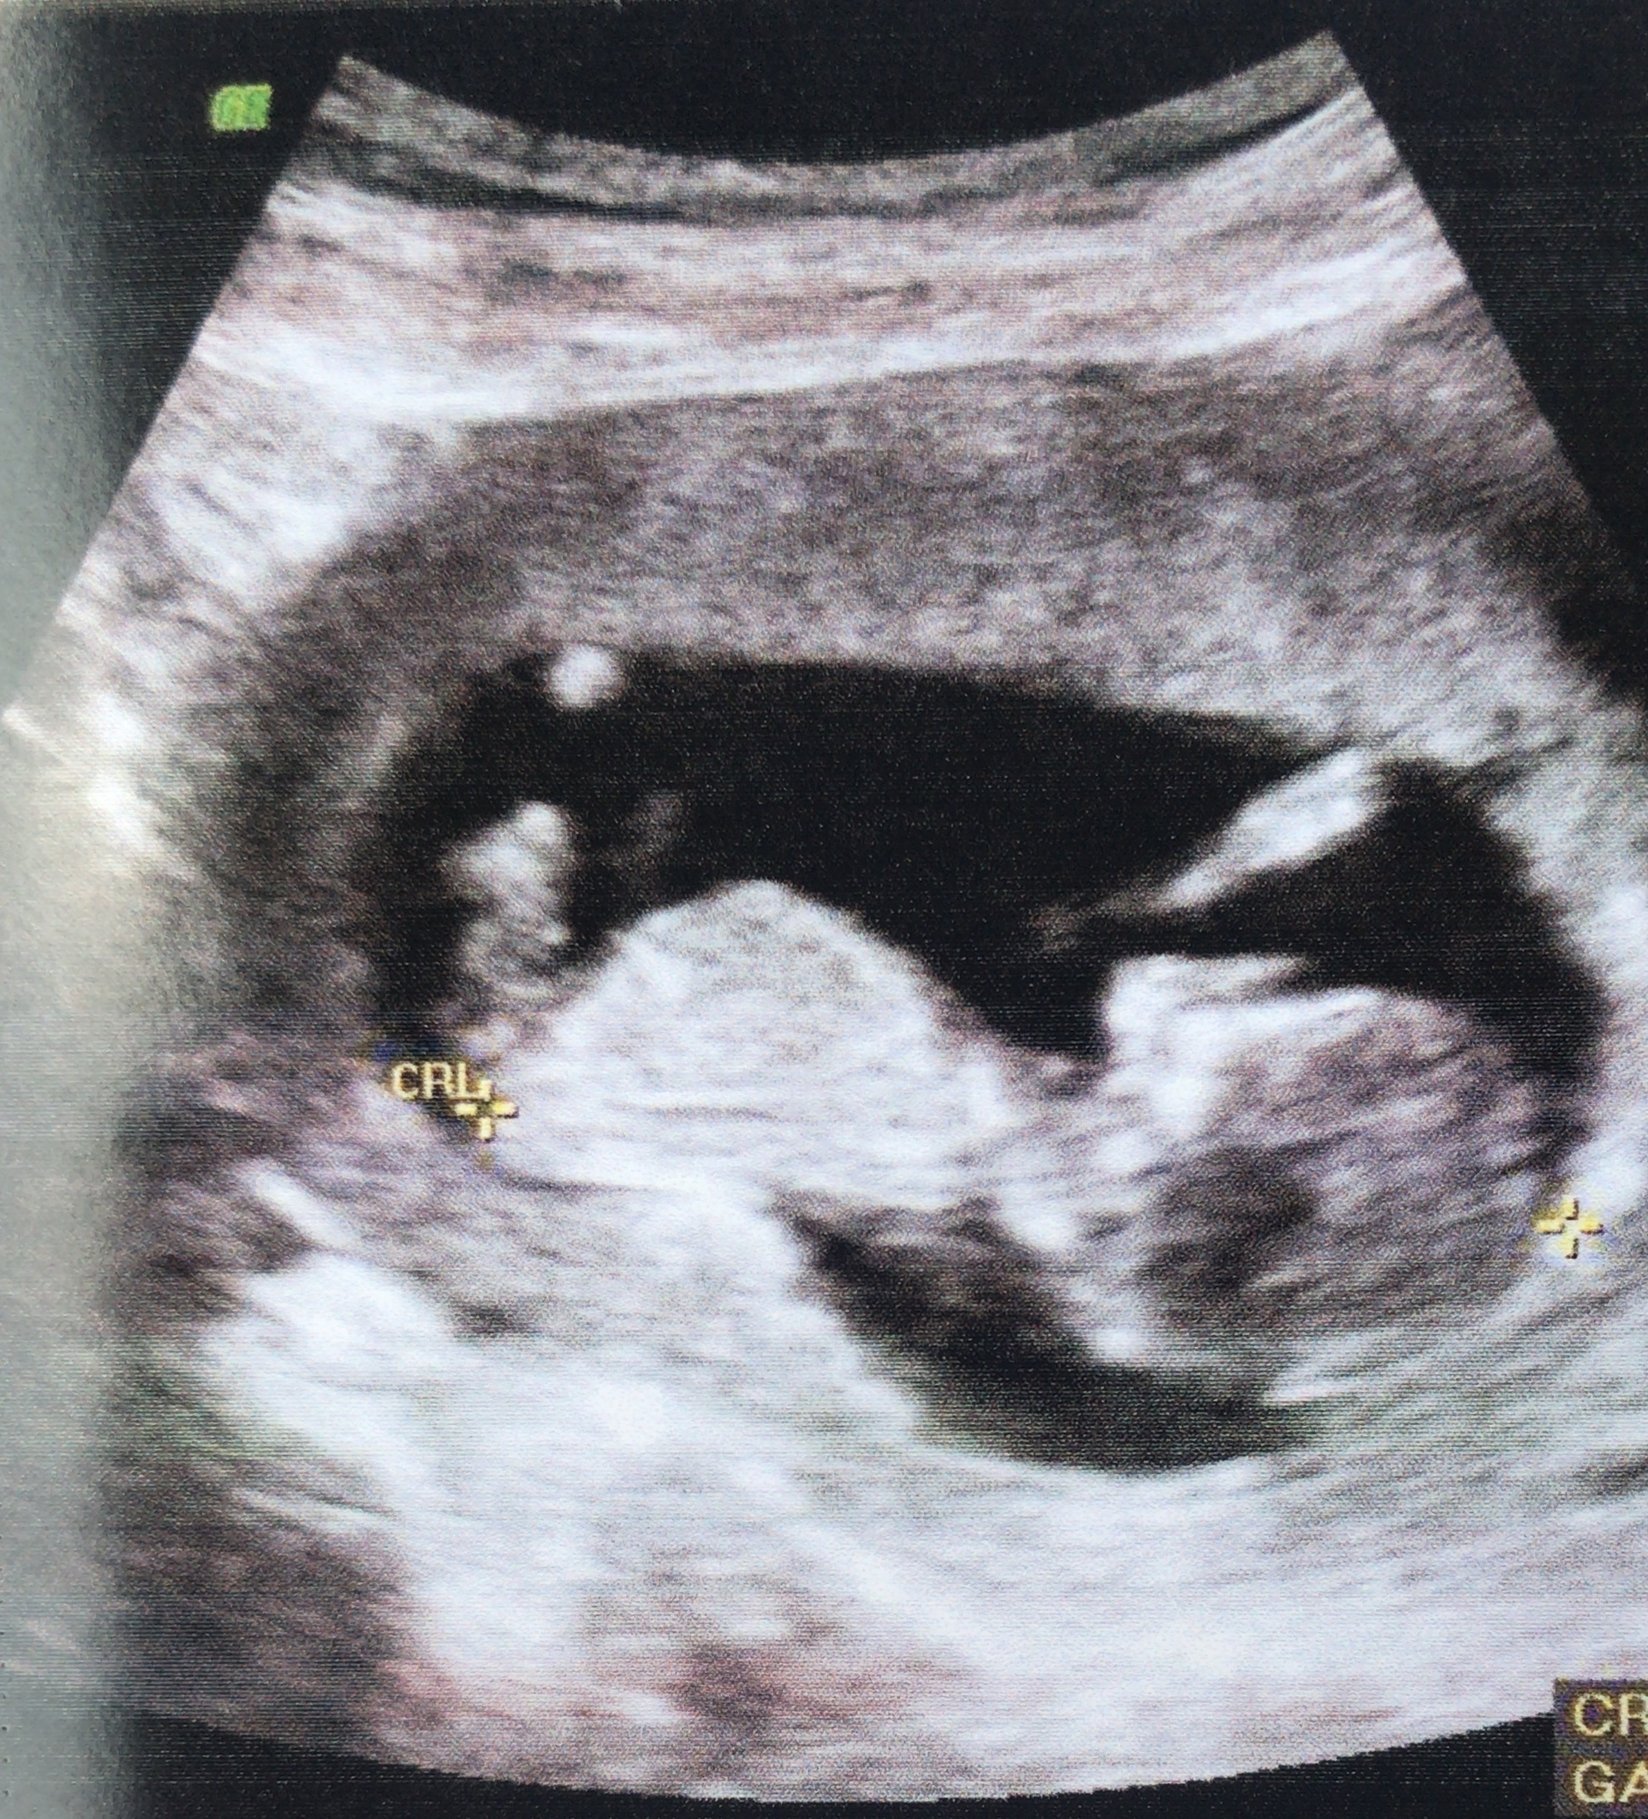

We had our first ultrasound at 10 weeks (I am 12 weeks now - due date at 11/19/18 - which is 3 days before my husband’s bday lol) I am a FTM, and thought this was so incredible. Seeing everything clearly definitely settled my nerves - the baby’s heart was fluttering at 154BPM and moving around like crazy! Our ultrasound tech showed us that she thinks it’s already a boy (my husband was THRILLED lol!) but we are waiting until W20 to confirm and before we start purchasing for the nursery. Now we can finally announce!